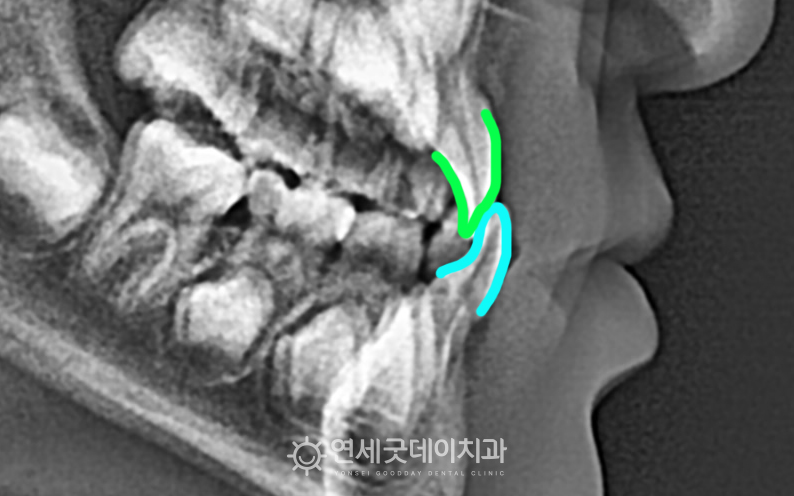

▲ 치료전 엑스레이

아랫니와 윗니가 거꾸로 물리는 어린이 반대교합이었으며,

하악 #32,42의 결손이 관찰되었습니다.